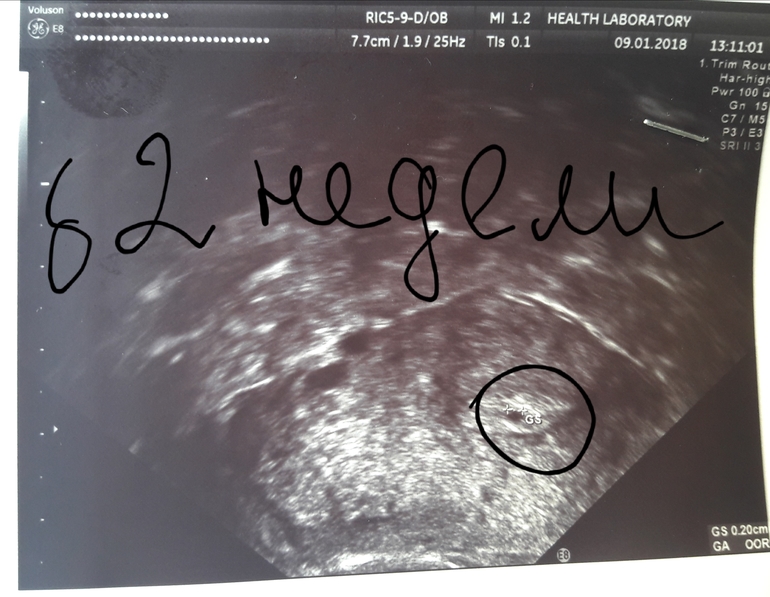

Р.S. Только что от гематолога.Сказала,нужно узи,есои ПЯ в матке не будет,то увы!Повела.Нас нашли!Правда мы совсем крошечные,но мы на месте!

А ваше я уже видела, поздравляю. Все будет хорошо!!